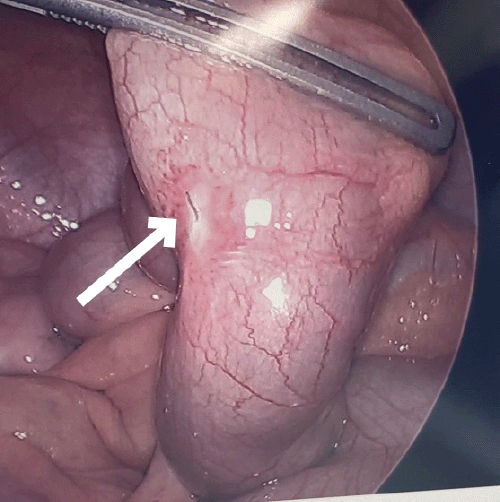

The patient was admitted to the hospital for observation; however, she did not improve with conservative therapy over 48 hours. Since the foreign body was located in the distal-terminal ileum, an attempt was made at endoscopic removal. At colonoscopy, the terminal ileum was successfully intubated; however, the foreign body could not be visualized. The next day, the patient continued complaining of right lower quadrant pain, and repeat CT imaging confirmed no progression of the foreign body within the gastrointestinal tract. At this point, the decision was made to proceed with diagnostic laparoscopy. The peritoneal cavity was entered using a 5 mm optical trocar in the left upper quadrant. The ligament of Treitz was identified, and the small bowel was run distally. At the terminal ileum, a filamentous metallic foreign body was identified protruding from the bowel wall approximately 20 cm from the ileocecal valve. The object was removed laparoscopically, and the site of perforation was repaired with imbricating sutures of 3-0 Vicryl in a Lembert fashion.

Figure 2. Two Views of Filamentous Metallic Foreign Body Perforating Terminal Ileal Bowel Wall (arrow). Published with Permission

Figure 3. Successful Removal of Metallic Foreign Body Using Laparoscopic Maryland Dissector. Published with Permission